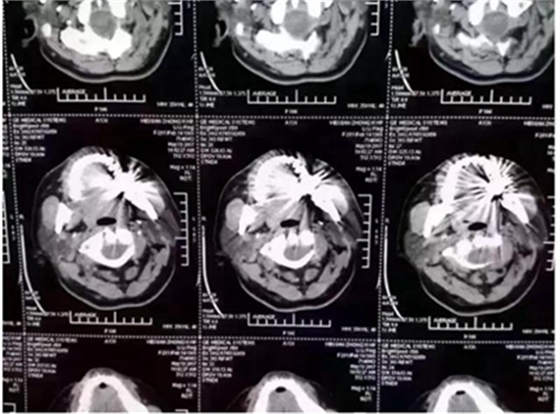

這幾天,一張照片刷爆了牙醫(yī)朋友圈

對(duì)這張照片,有牙醫(yī)評(píng)論如下:

口內(nèi)有金屬烤瓷牙做核磁共振,CT,以烤瓷牙為中心呈現(xiàn)放射狀影像,無法看清周圍組織,影響臨床診斷,建議條件允許的朋友還是選擇二氧化鋯全瓷冠修復(fù),以免帶來不必要的麻煩!

2.因金屬內(nèi)冠的存在,透光性、色澤和形態(tài)與自然牙存在較大的區(qū)別,更會(huì)在燈光下產(chǎn)生青灰色的效果。同時(shí)金屬瓷牙在液體口腔酸堿環(huán)境細(xì)菌作用下不穩(wěn)定,患者在做CT核磁共振時(shí)金屬有一定的干。